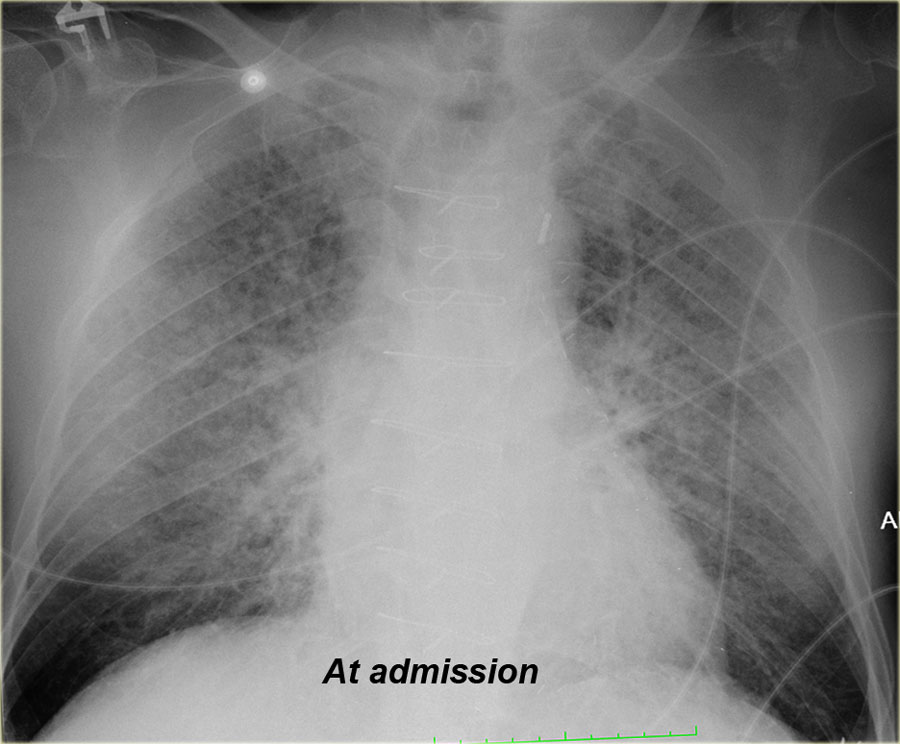

- Chest X-ray to look for fluid in the lungs

- Radiology Assistant. (2024). Chest X-ray in Heart Failure. https://radiologyassistant.nl/chest/chest-x-ray/heart-failure